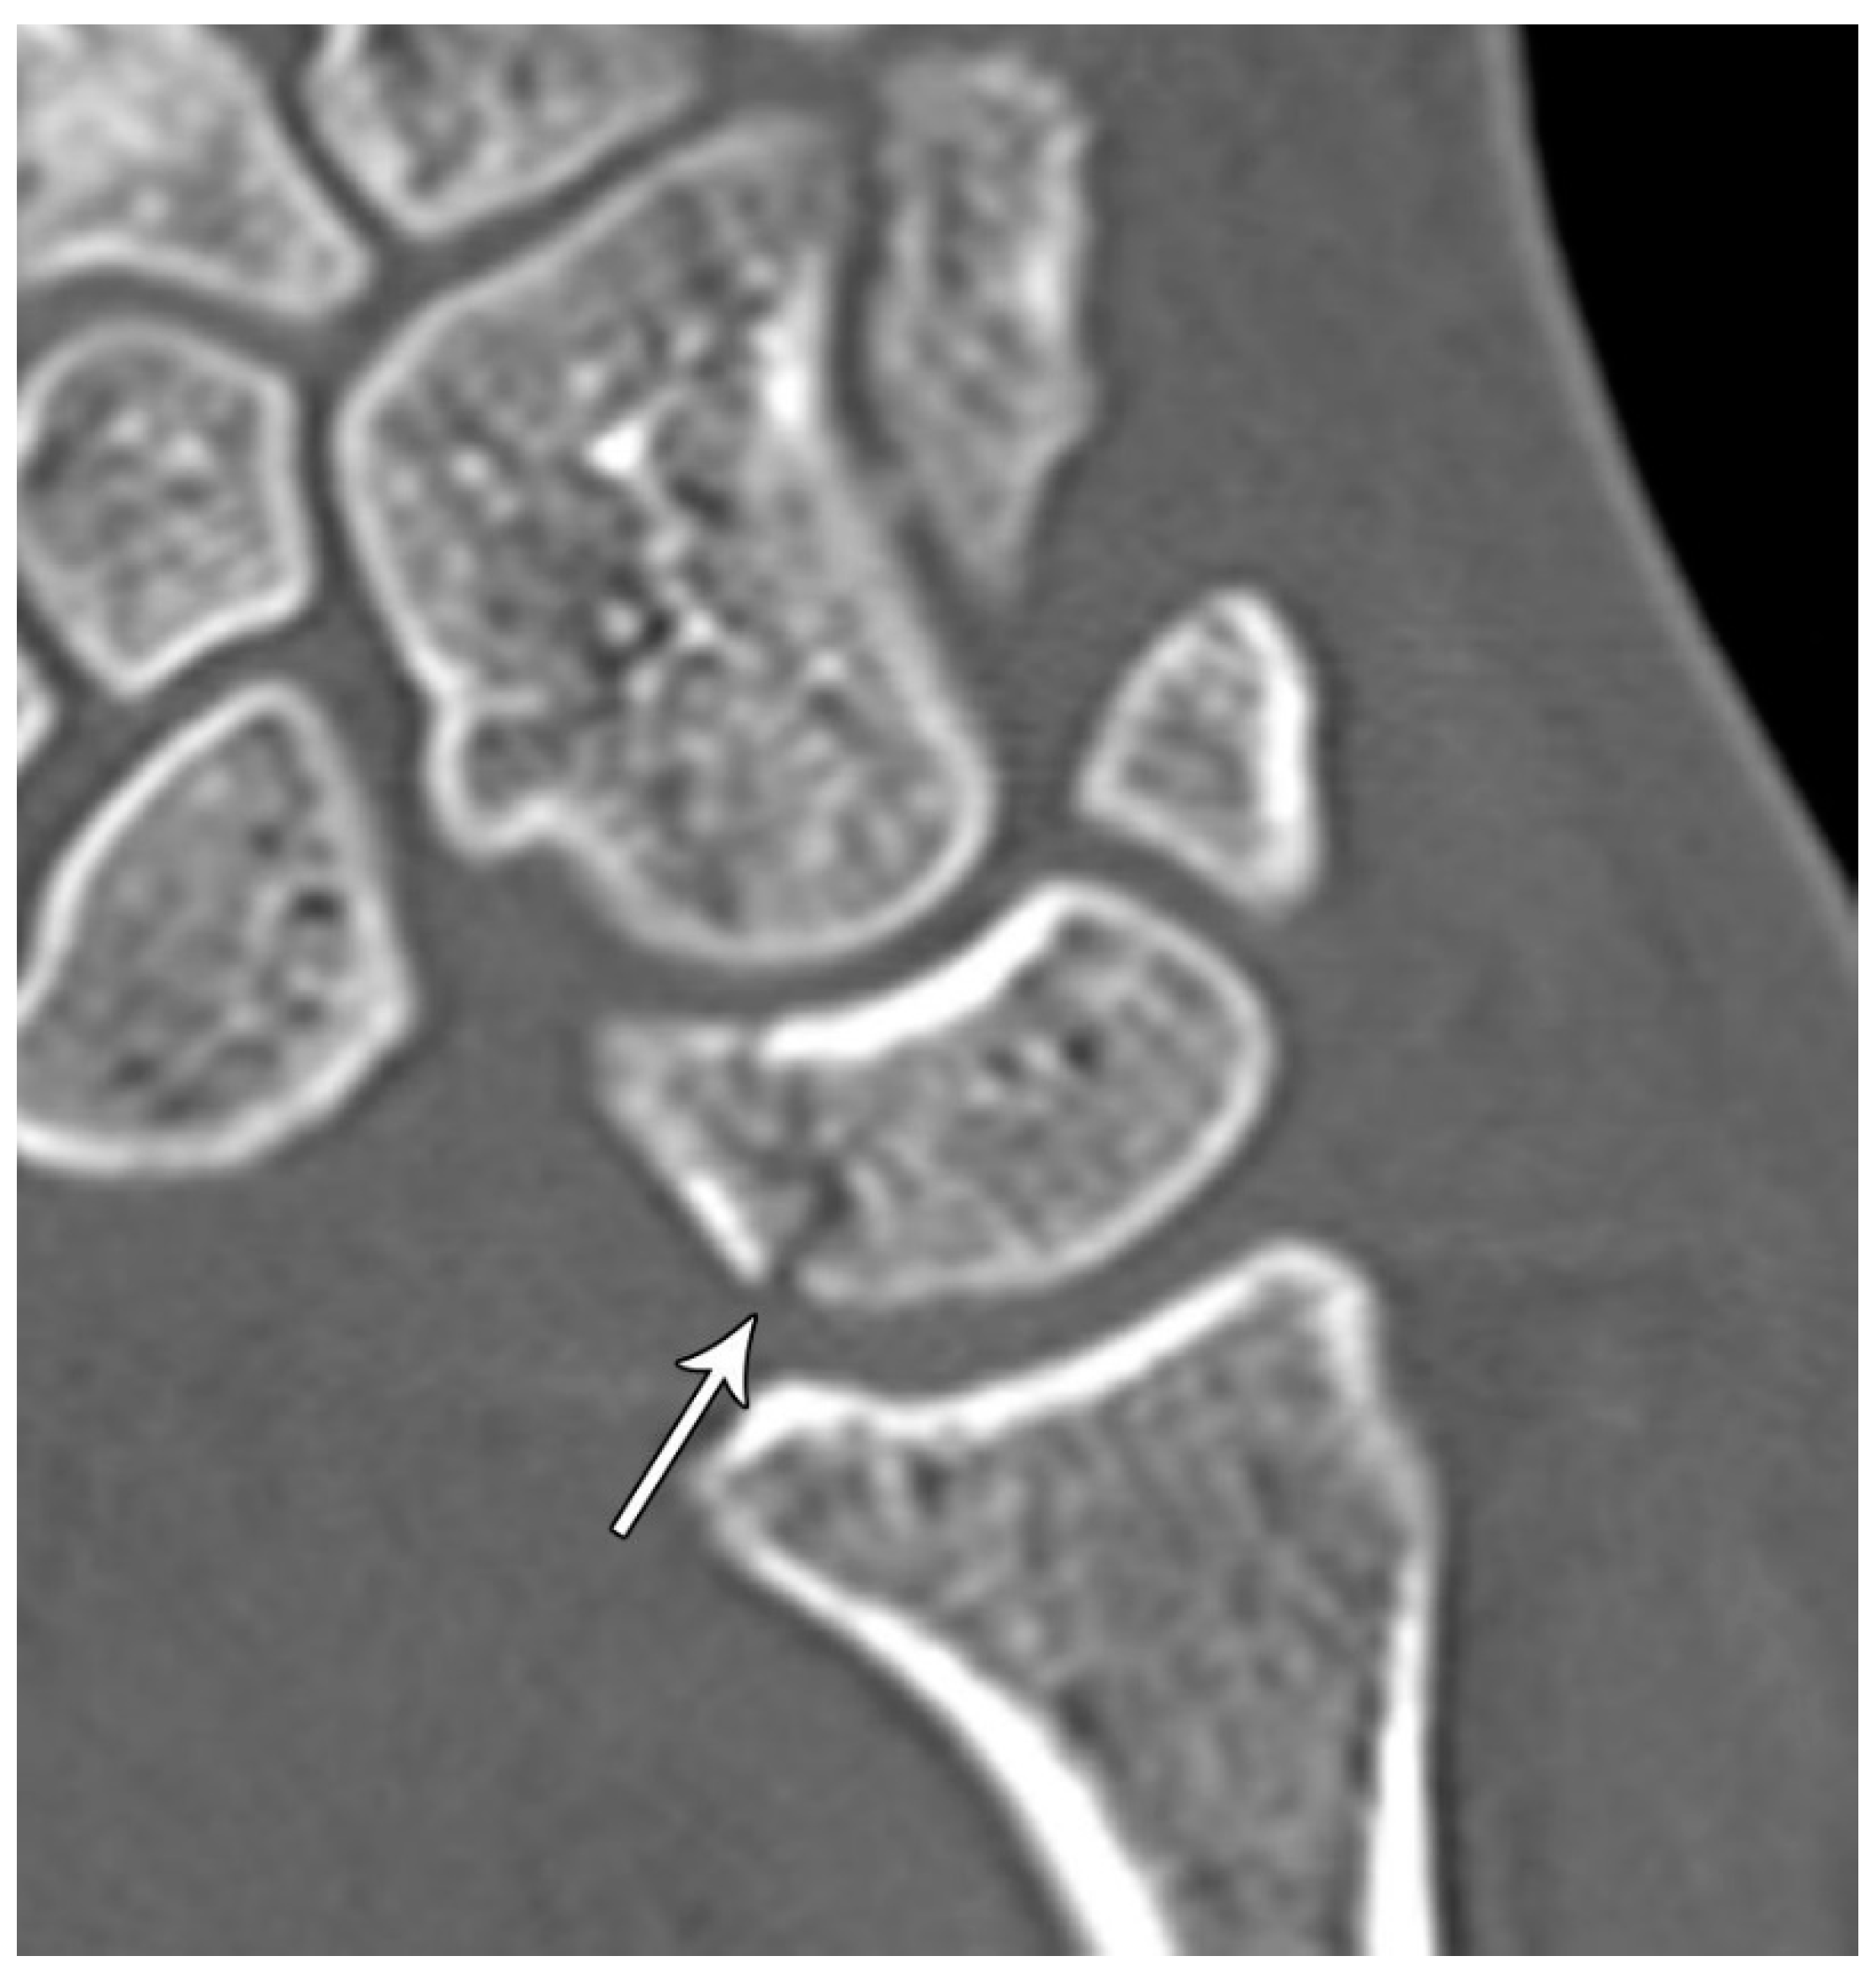

Lunate fractures are categorized as volar pole, dorsal pole, transverse, osteochondral, and transarticular (Figure 16). Volar pole lunate fractures are the most common and are due to the axial compression from the capitate with the wrist in dorsiflexion and ulnar deviation and additionally may lead to volar intercalated segment instability (VISI) [21]. Like the scaphoid and capitate, the proximal lunate is susceptible to vascular compromise in trauma, with up to 20% of people having only a single palmar nutrient artery supplying the entire lunate. Management of stable, nondisplaced lunate fractures consists of 4-6 weeks of immobilization. Surgical management is indicated for displaced fractures and those with concomitant scapholunate ligament or lunotriquetral ligament injury to preserve the existing anatomy and ensure stability. Chronic fractures with advanced arthritis may even call for partial fusion or proximal row carpectomy [10].

Figure 16. Sagittal reformatted CT of the wrist showing transarticular lunate fracture (arrow).